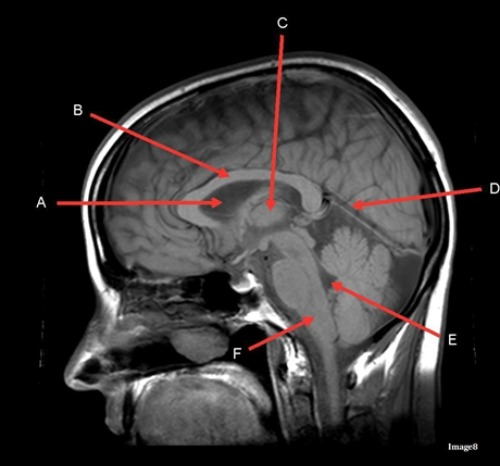

Letter C in image 8 is pointing to:

A. Tentorium

B. Corpus callosum

C. Thalamus

D. Fourth Ventricle

E. Medulla oblongata

Letter D in Image 8 is pointing to:

B. Cerebellum

Letter A in Image 8 is pointing to:

C. Hypothalamus

E. Lateral Ventricle

Image 8 is an example of a ____ weighted sequence acquired in the ____ scan plane.

A. T1; Axial

B. T1; Sagittal

C. T2; Axial

D. T2; Sagittal

Letter D in Image 14 is pointing to:

B. Sphenoid sinus

C. Frontal Sinus

D. Sagittal sinus

E. Fornix

Letter B in Image 14 is pointing to:

A. Corpus callosum

B. Third ventricle

C. Lateral ventricle

D. Pituitary gland

Letter C in Image 14 is pointing to:

Letter B in Image 8 is pointing to:

Letter E in Image 8 is pointing to:

Letter F in Image 8 is pointing to: